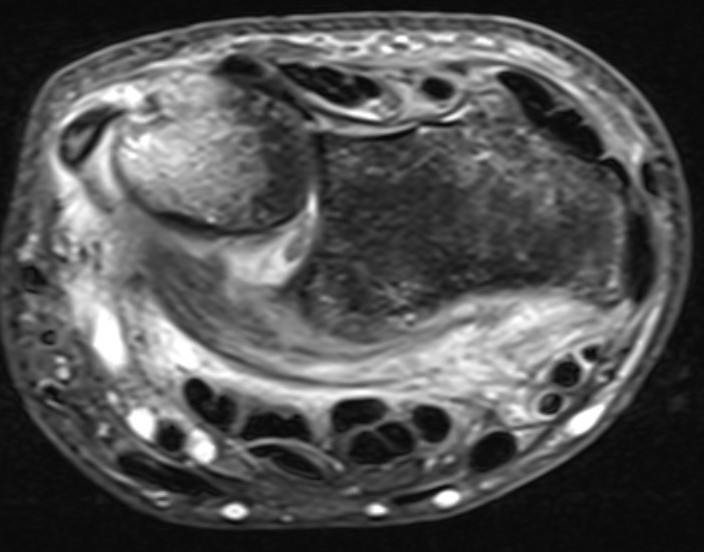

MRI demonstrating dorsal distal ulna subluxation associated with significant ligament disruption

Ulna styloid process fracture and acute DRUJ instability

Ulna styloid fracture with TFCC injury